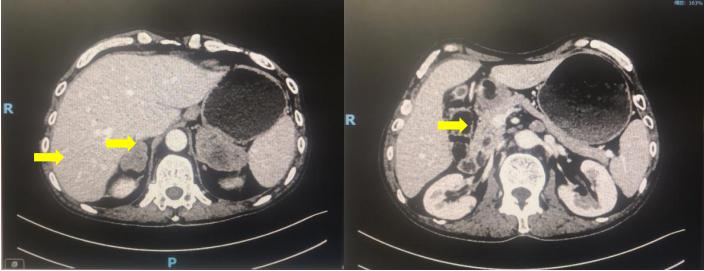

患者为男性, 64 岁,2019 年 06 月因腹胀 6 天、肛门停止排气排便 3 天在外 院就诊,CT 检查提示空肠恶性肿瘤及双侧肾上腺占位。2019 年 06 月 25 日在首 都医科大学附属北京世纪坛医院全麻行腹腔镜下小肠部分切除术,术后病理示:小肠低分化癌,淋巴结转移灶符合低分化腺癌。(部分小肠及肿瘤)结节样肿瘤 组织,瘤细胞圆形、卵圆形,胞浆红染,核重度异型,部分核偏位,核仁明显, 核分裂易见。呈实性片状排列,伴大片坏死,瘤组织累及黏膜下层、肌层及浆膜 层,局部累及黏膜层;两端切缘未见肿瘤,可见脉管癌栓,未见神经侵犯;肠周 淋巴结转移性肿瘤(2/12),(肠系膜淋巴结)淋巴结未见转移性肿瘤(0/1);免 疫组化结果:(B4)CK(+), VIM(+), CD117(-), CD34(-), Dog-1(-), SDHB(+), SMA(-), Desmin(-), S-100(-), SOX-10(-), HMB45(-), MelanA(-), Myoglobin( 部 分 +), Ki-67(90%), P53( 个别阳 性 ), PD-L1(SP142)(TC 70%, IC5%+), PD-1(UMAB199)(个别阳性), CD21(-)。基因检测:KRAS, EP300, SMARCA4, KEAP1, GEN1, TGFBR2, WRN, SLX4, STK11 基因存在有意突变;MSI 状态:MSS;肿瘤突变负荷 17.4mut/Mb。术后恢复可,现来我院继续治疗。个人史、既往史、家族史无特殊。2019 年 7 月 22 日术后复查 CT 可见双侧肾上腺转移,腹膜后淋巴结多发转移。

疗效评估 :一线 Xelox 方案化疗 2 周期后肾上腺肿瘤明显退缩,腹膜后淋巴结明显缩小,疗效评估(PR),一线方案治疗 6 周期后疗效评价(SD),肿瘤稍增大;一线治疗 4 周期后血 CA199 出现回升,6 周期治疗后 CA199 明显升高。